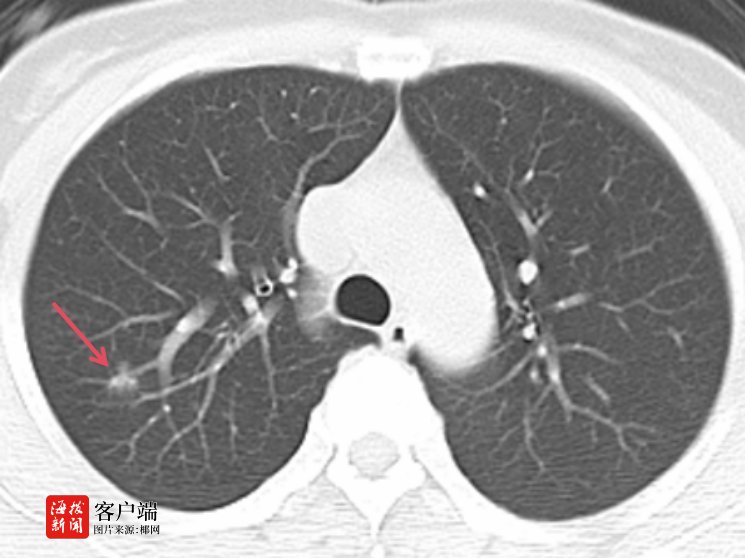

商报全媒体讯(椰网/海拔新闻记者 孙鑫 通讯员 杨树博 赵宏光)随着胸部CT筛查的广泛应用,越来越多的肺磨玻璃样结节被发现。49岁的患者李女士在去年的一次常规体检中,胸部CT扫描发现她的右肺上叶有一个约11mm×10mm的小结节,且该结节呈磨玻璃样改变。医生告诉她,这可能是肺癌的早期迹象——具有生长缓慢,浸润不强,不发生转移,切除后也不会复发等特点。这个消息像晴天霹雳,让李女士陷入了恐慌。

对李女士的病情,赵宏光主任团队高度重视,在吴毓优主任医师、刘运仲副主任医师的配合下,赵宏光主任精准阅片,分析肺段结构后,决定为其行胸腔镜下右上肺后段切除术。

为什么李女士的肺结节要做肺段切除呢?赵宏光主任介绍说,李女士的肺结节远离肺表面,手术中难以触及,无法行肺楔形切除术,只能行肺段切除术。肺段手术技术要求高,不但需要术前对肺结节进行精准的肺段定位和手术规划,还要求术者具有极强的解剖知识、手术技能和处理手术意外情况的经验,术中也要精细、精准。无论哪一环节出现问题,手术都难以进行。

术前,赵主任团队分析肺段动脉、静脉及支气管,并准确定位结节位置,精准分析切除范围,制定肺段切除计划。术中,由于李女士叶间裂发育不全,给后段切除手术造成了一定阻碍,但赵宏光主任凭借着坚实的解剖知识及高超的手术技巧和丰富的手术经验,清晰地将各个结构分离并离断各支肺段动脉、静脉及支气管,精准地切除右上肺后段。